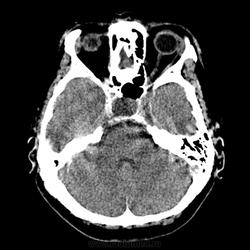

образование средней черепной ямки справа, образование турецкого седла?

женщина. 58 лет. жалобы на головные боли. саму пациентку не видел. в карте о вмешательствах на черепе ничего нет. что скажете по данным снимкам?

Да.